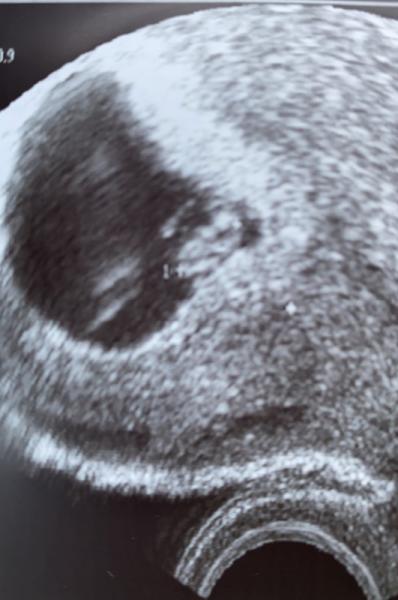

Und ich dürfte eine kleines Herzchen schlagen sehen. Ich bin soo glücklich Wurde zwar 2 Tage zurück datiert aber ich hoffe das trotzdem alles ok wird.

Bild zu Zurück vom Arzt.. - Forum für Juli - Mamis

Sehr schönes Bild freue mich für dich!